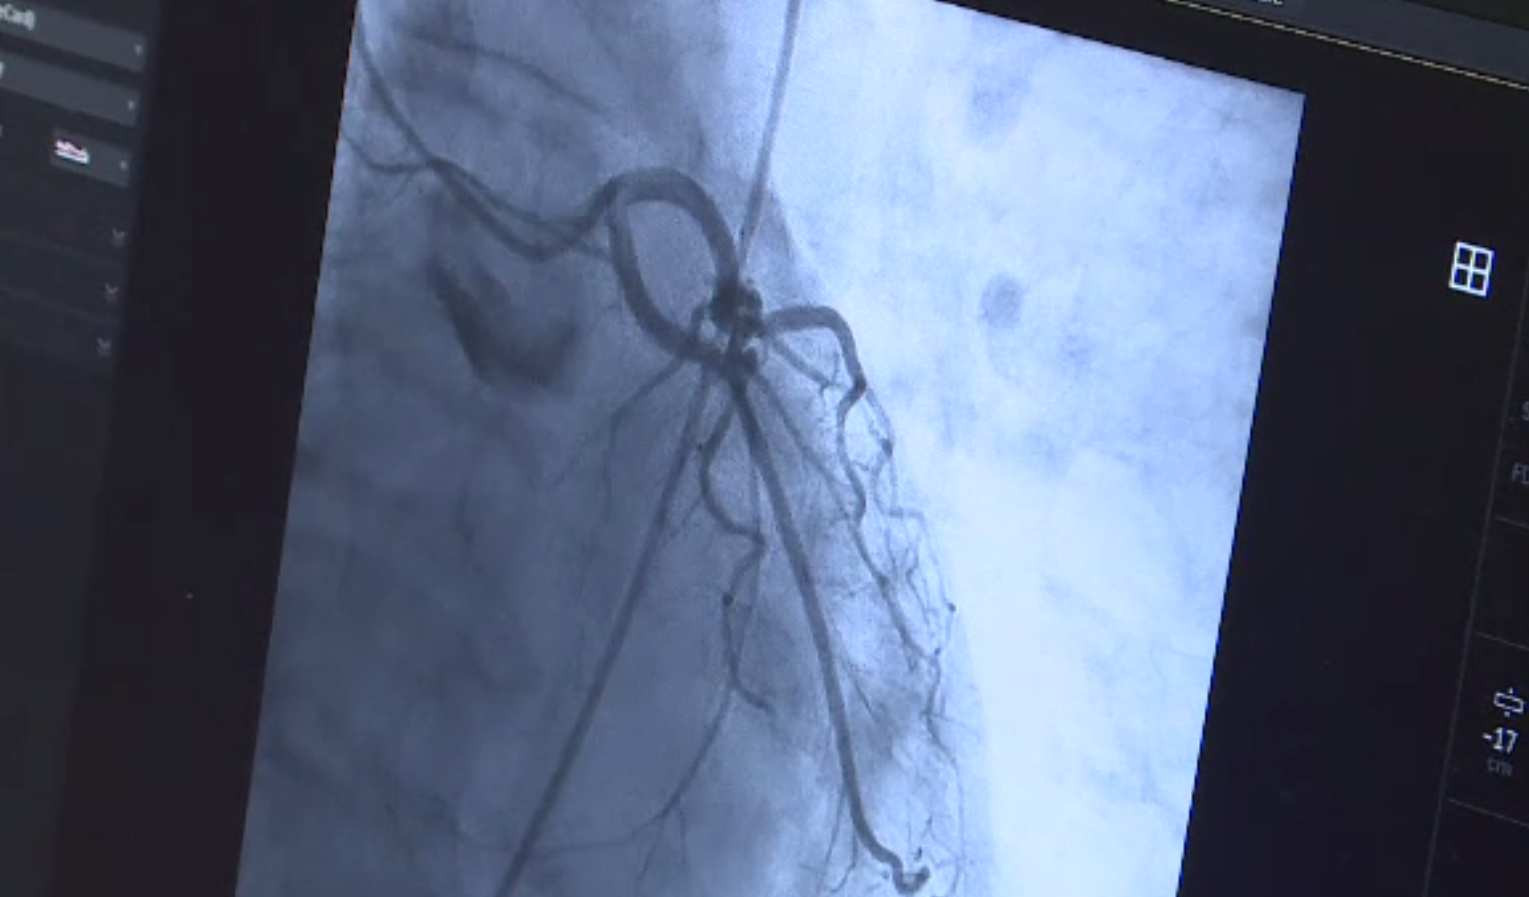

Intervenție complicată la Institutul CC Iliescu. Cateter și stent introdus prin vena femurală, inimă și artera pulmonară

Vorbim acum despre o intervenţie complicată, care a avut loc, în premieră, la Institutul CC Iliescu, din Capitală.